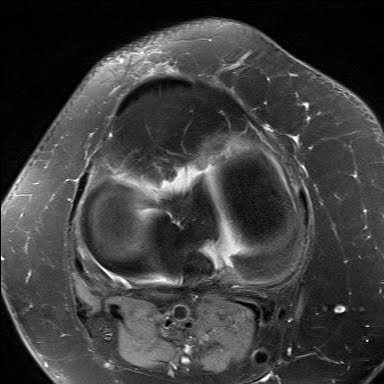

Radial Tear Posterior Medial Meniscal Root

Labels: MRI, MSK, Posterior Root, Radial Tear, Root Tear